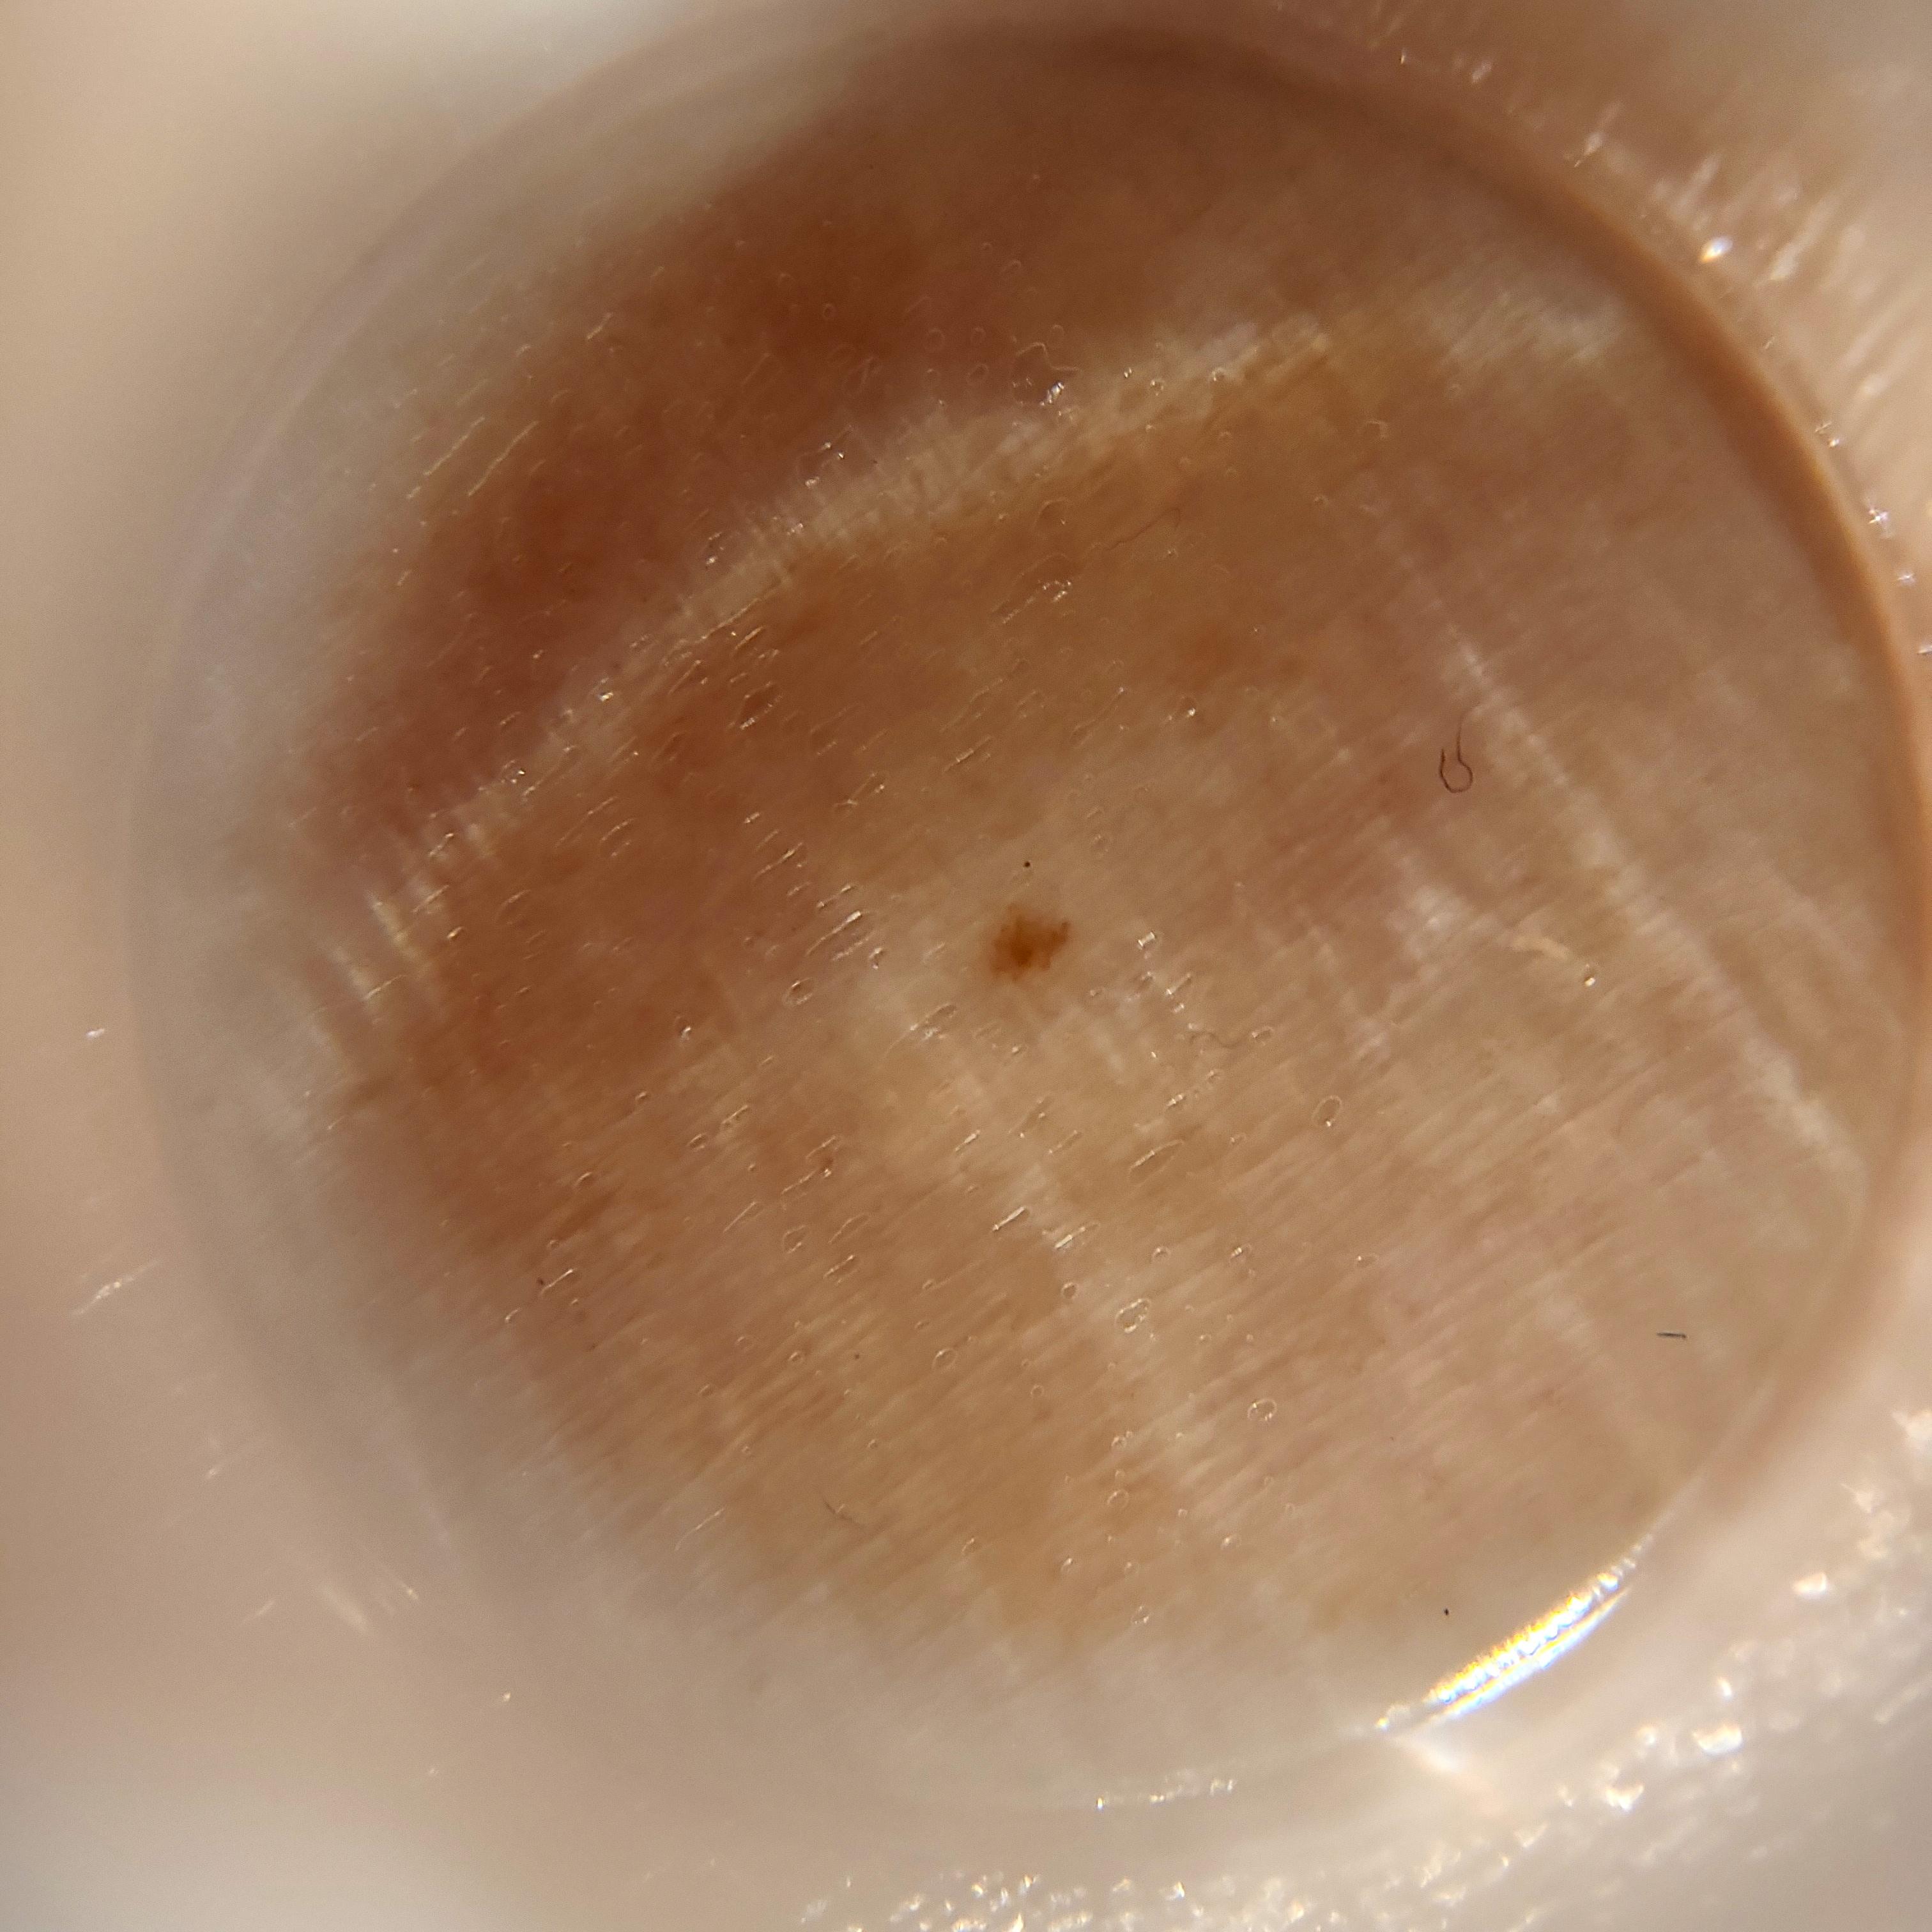

ISIC_1803958

1422 x 1422

Clinical

Field Value

acquisition_day 112

age_approx 45

anatom_site_1 Upper extremity

anatom_site_general upper extremity

diagnosis_1 Benign

diagnosis_confirm_type single image expert consensus

image_type dermoscopic